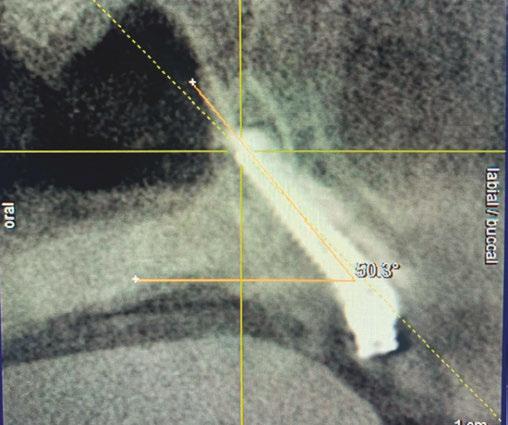

The development of Unifi MI for dentistry

Taking cues from the tremendous successes in the medical field, a project started a few of years back with idea to apply this technology to dental implants. The forces the implant will be exposed to are similar to those in medicine with regard to toggling forces, but would differ in axial forces. In dentistry, these forces would be exerted in a compressive fashion down the implant body as opposed to the screws used in the other medical disciplines which are subjected instead to massive pull-out forces. Due to this fundamental difference, the usually “upward” facing Unifi threads were flipped into a downward facing position. To assure there would not be any mechanical disadvantage or change in stress distribution, finite element analysis (FEA) was conducted (Figure 4).